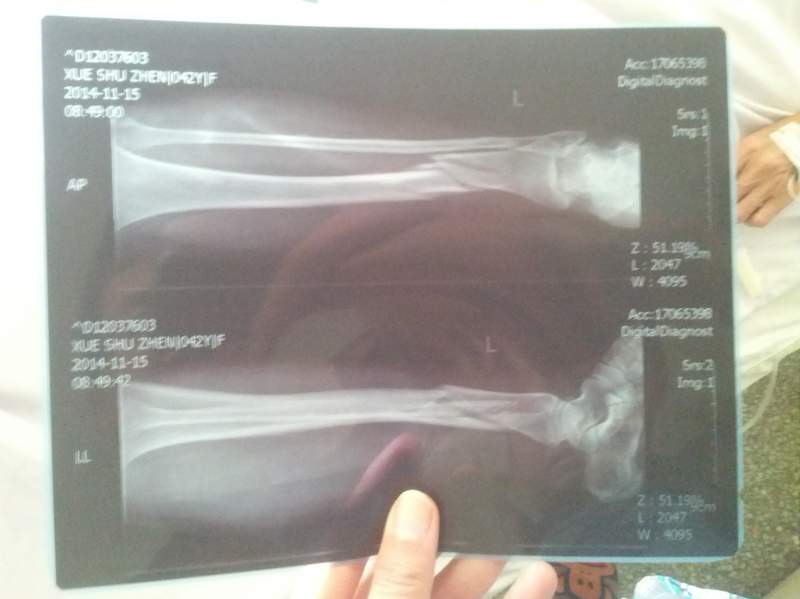

妈妈今年51岁,11月15号左胫腓骨骨折了,24号做了手术,加了两个钢板,现在脚还是肿的厉害。 请教问一下各位老师,现在需不需要开始做康复训练,可不可以麻烦各位老师帮忙制定一下。我把片子传上来 IMG_20141118_082401.jpg IMG_20141126_161505.jpg |